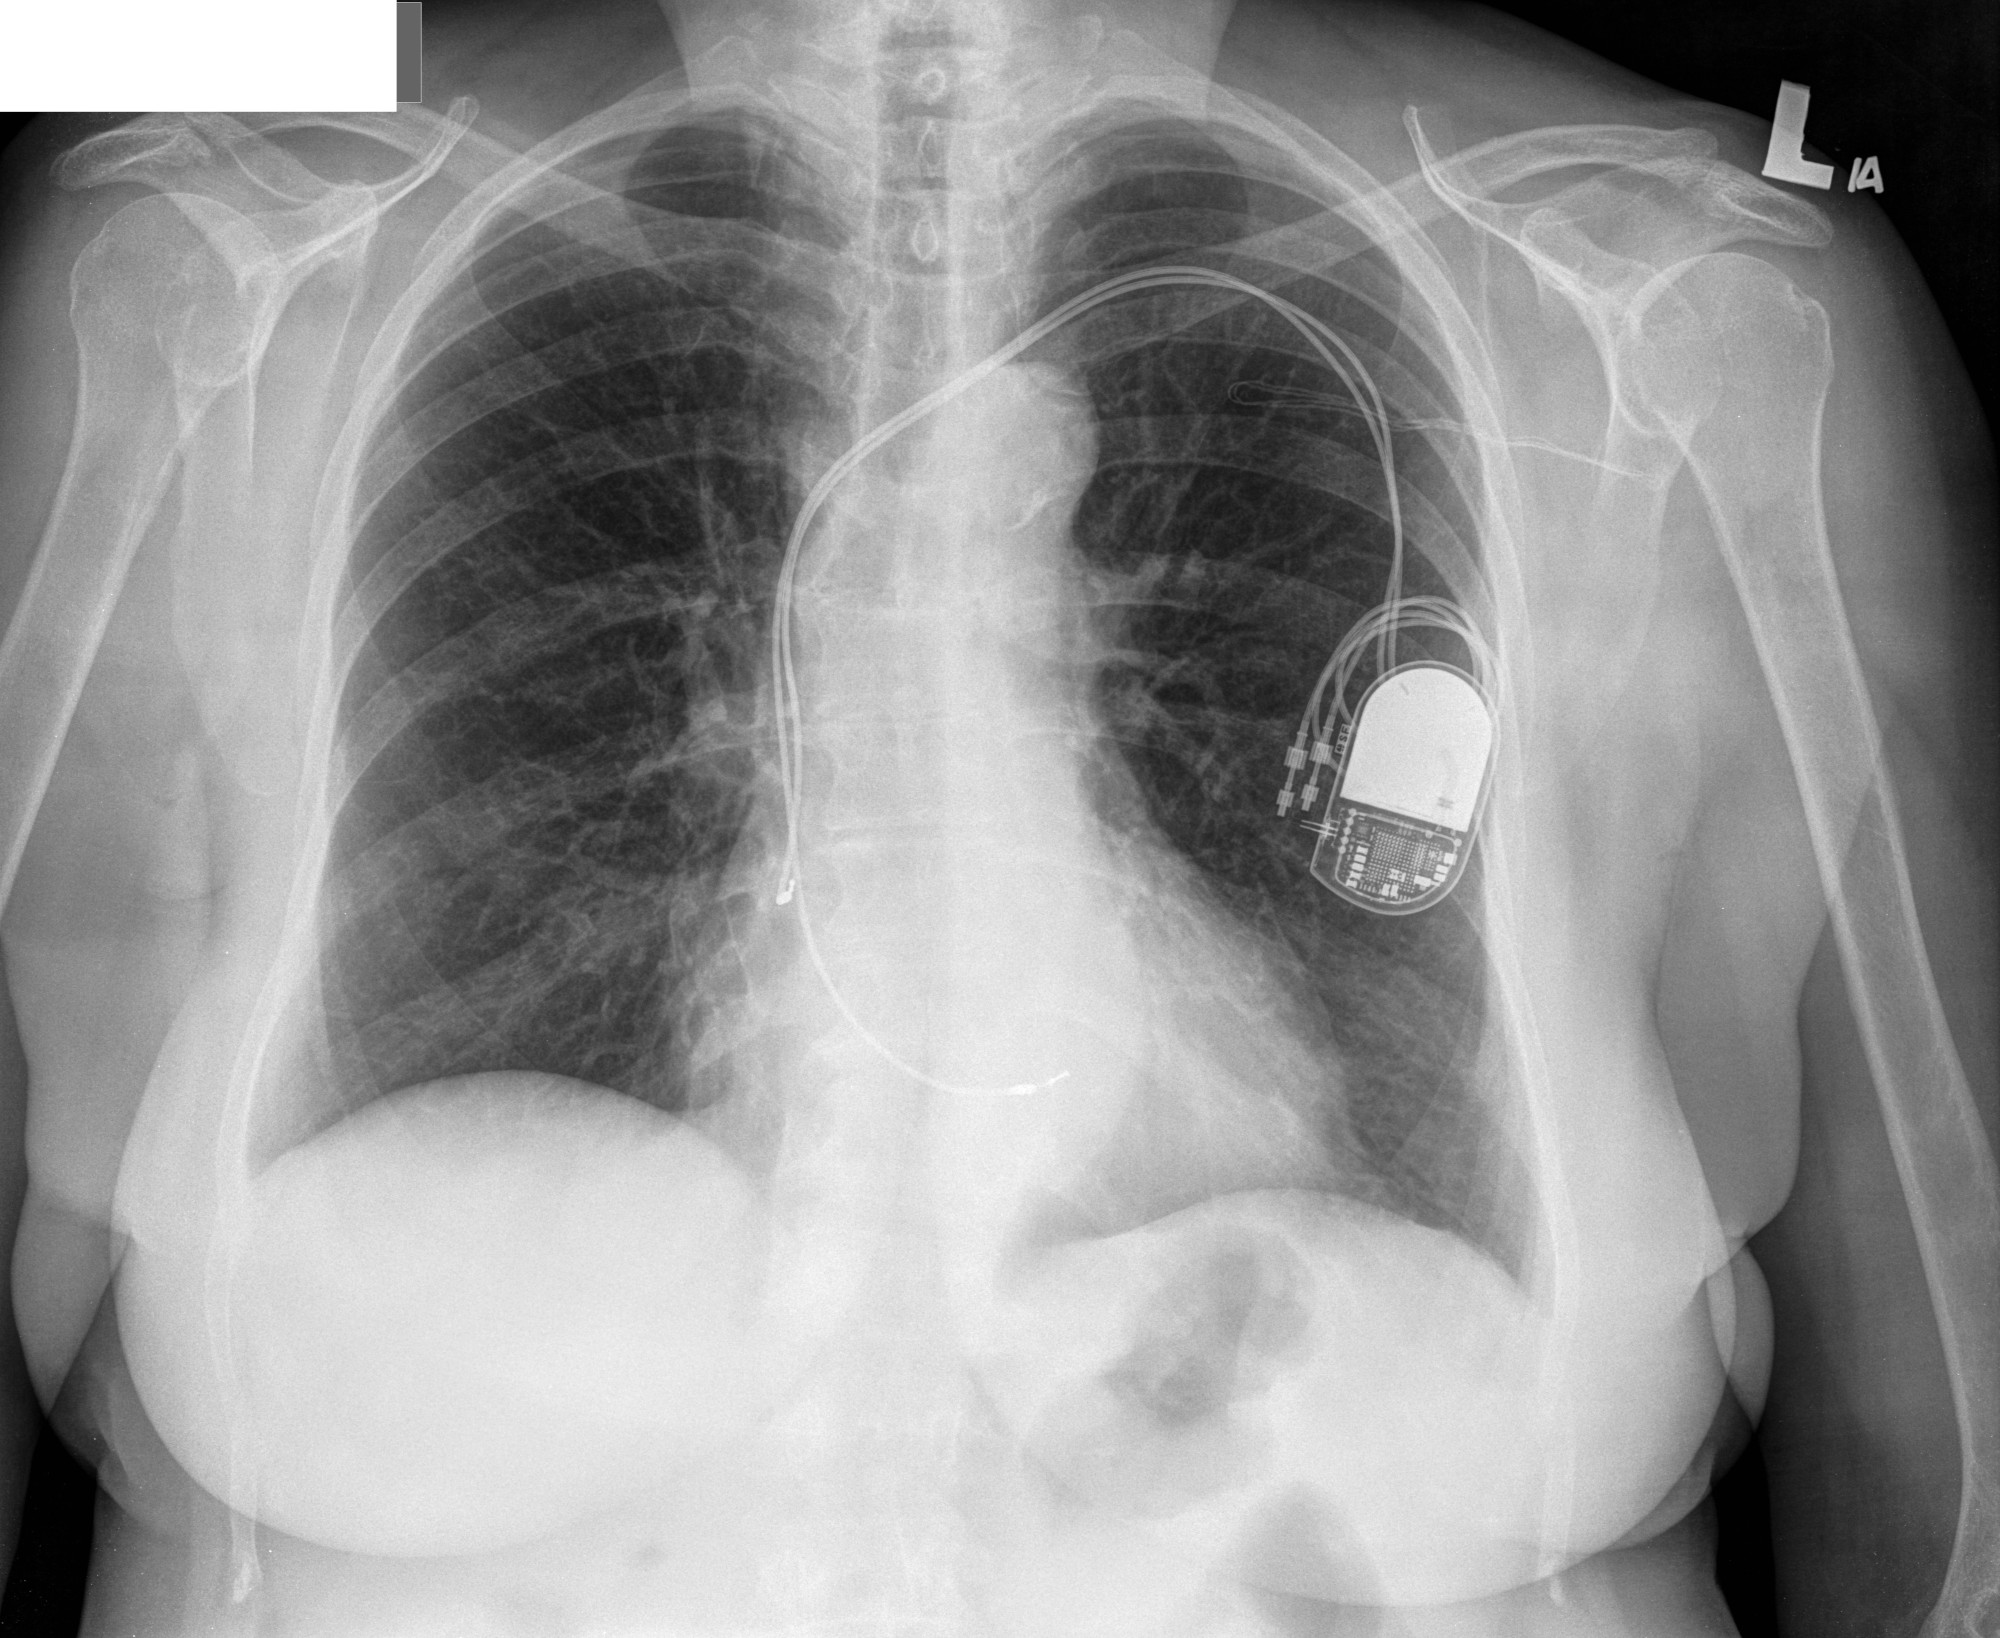

ICD

icd.jpg